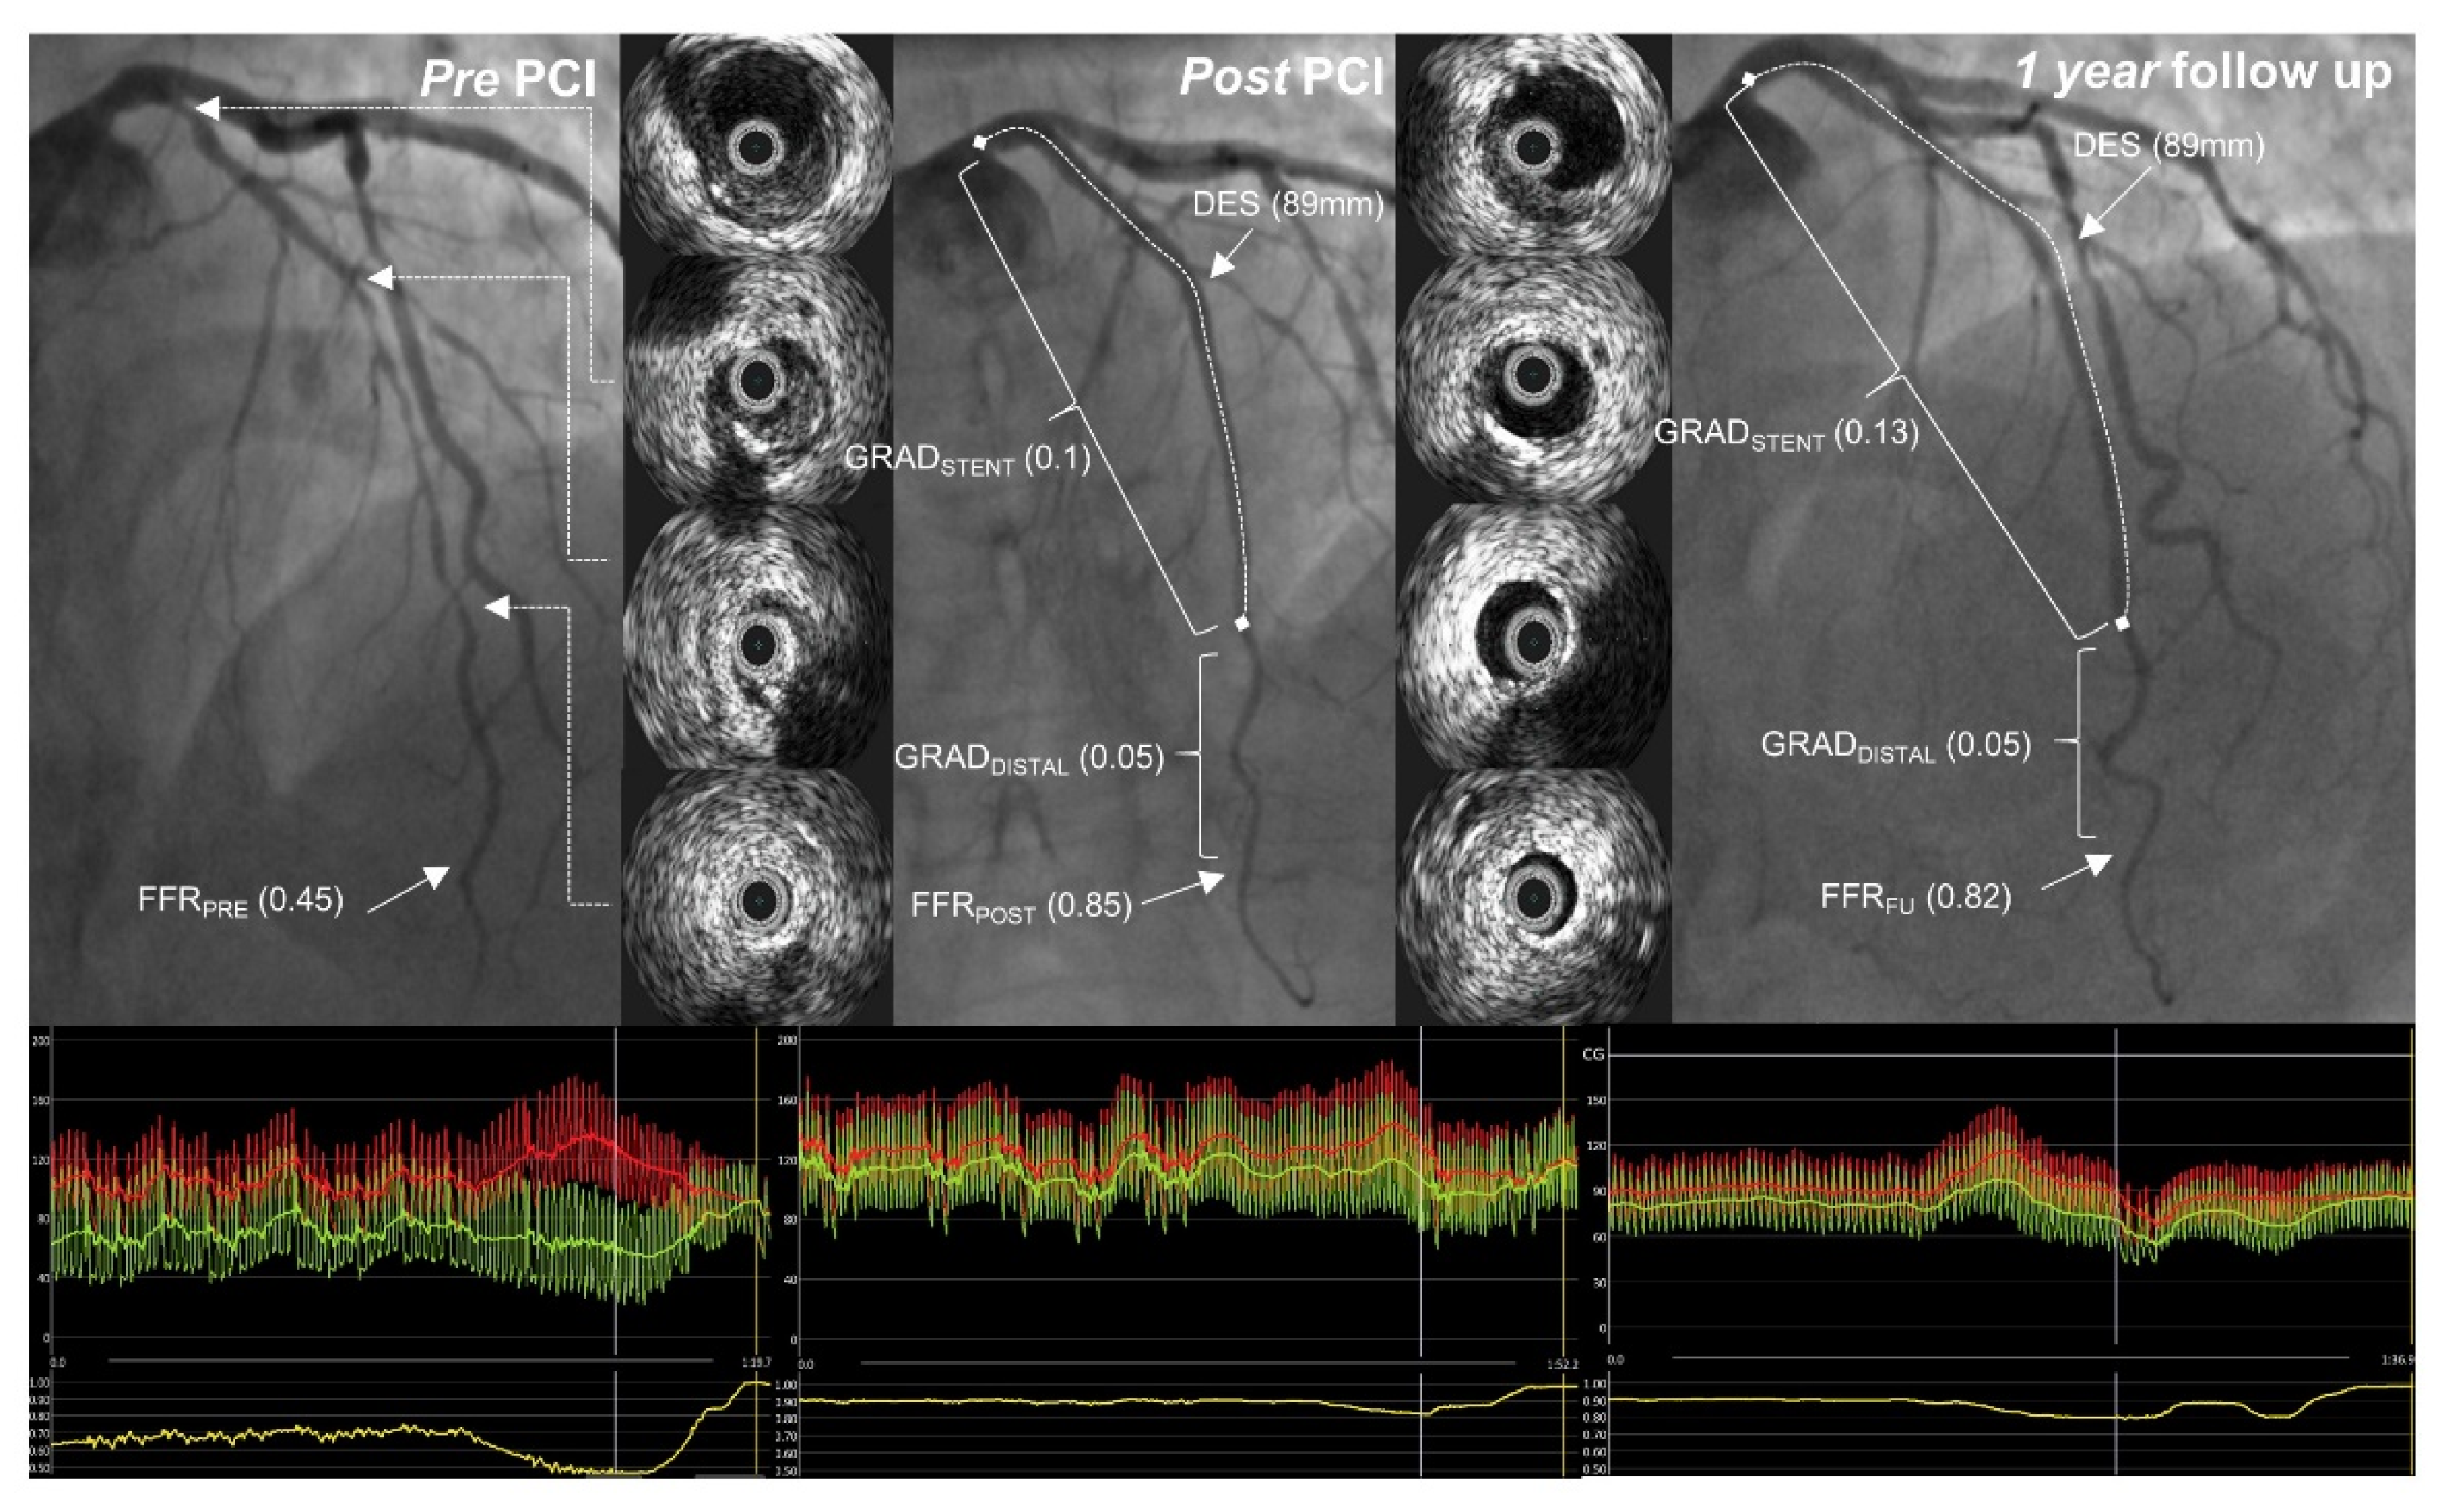

Before performing PCI, IVUS was utilized to determine the ideal stent implantation spots, aiming for locations with a plaque volume of less than 50%. The stent diameter was selected based on the distal external elastic membrane diameter minus 0.25 mm (Figure 2). IVUS also aided operators in selecting the proper tools for lesion pre-dilatation. The Eagle Eye Platinum IVUS catheter (Philips, Cambridge, MA, USA) was employed for IVUS procedures.

Figure 2.

A case example. Pre-, post-percutaneous coronary intervention (PCI) and one-year follow-up angiographic images with intravascular ultrasound pictures from a corresponding left anterior descending artery segment. Fractional flow reserve curves are presented below. FFRPRE—FFR before PCI; FFRPOST—FFR post-PCI; GRADDISTAL—distal gradient (from the distal segment to the distal stent edge); GRADSTENT—trans-stent gradient; FFRFU—FFR recorded at follow-up.

Operators aimed to achieve an optimal anatomical outcome during PCI, guided by IVUS assessment using the following criteria: (1) ensuring proper stent apposition, (2) achieving adequate stent expansion (with a minimal stent area (MSA) greater than 90% of the distal reference lumen area and/or MSA of at least 5.5 mm2), (3) maintaining a plaque burden below 50% within 5 mm proximally and distally to the stent, and (4) avoiding stent edge dissection. A case example demonstrating stent expansion and apposition is demonstrated in Figure 3 and Figure 4.